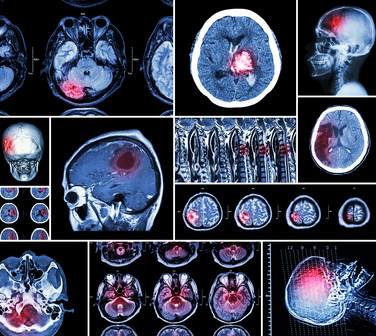

El objetivo principal es incidir en los puntos clave en el protocolo de diagnóstico por la imagen en el infarto cerebral. Inicialmente es importante revisar las diferencias entre el manejo diagnóstico del infarto cerebral respecto al infarto de miocardio. En segundo...